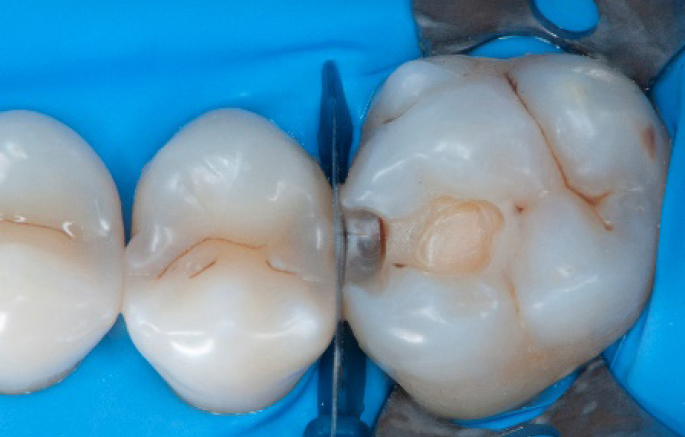

Step 10:

The situation after the application of SDR® flow+ material.

Step 11:

Occlusal surface restored using Spectra ST4 composite in shade A2.